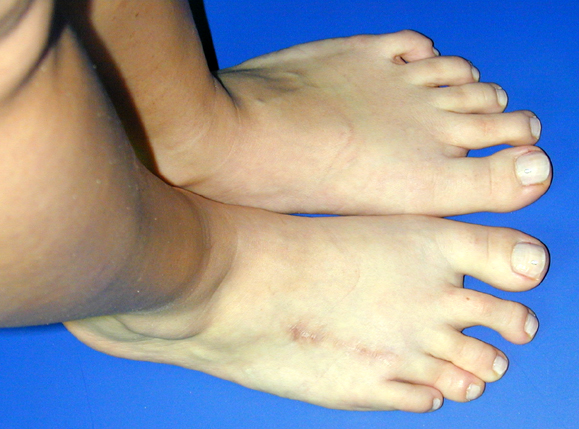

El parmağı (metakarp) ve ayak parmağı (metatars) kısalıkları doğuştan tek başına, geniş bir sendrom grubuyla birlikte, travma sonrası, Freiberg hastalığı (avasküler nekroz) sonrası görülebilir.

Metakarp kısalığında kozmetik görünümün bozulması ve dominant elin kullanımı sırasında yorulma, metatars kısalığında ise kozmetik haricinde metatarsalji, kısa parmağın dorsale kayması sonucu deformite oluşması, plantar yönde açılanması sonucu ağrı ve bası ülserleri, ve ayakkabı giymede zorluk nedeniyle ameliyat gerekebilir.